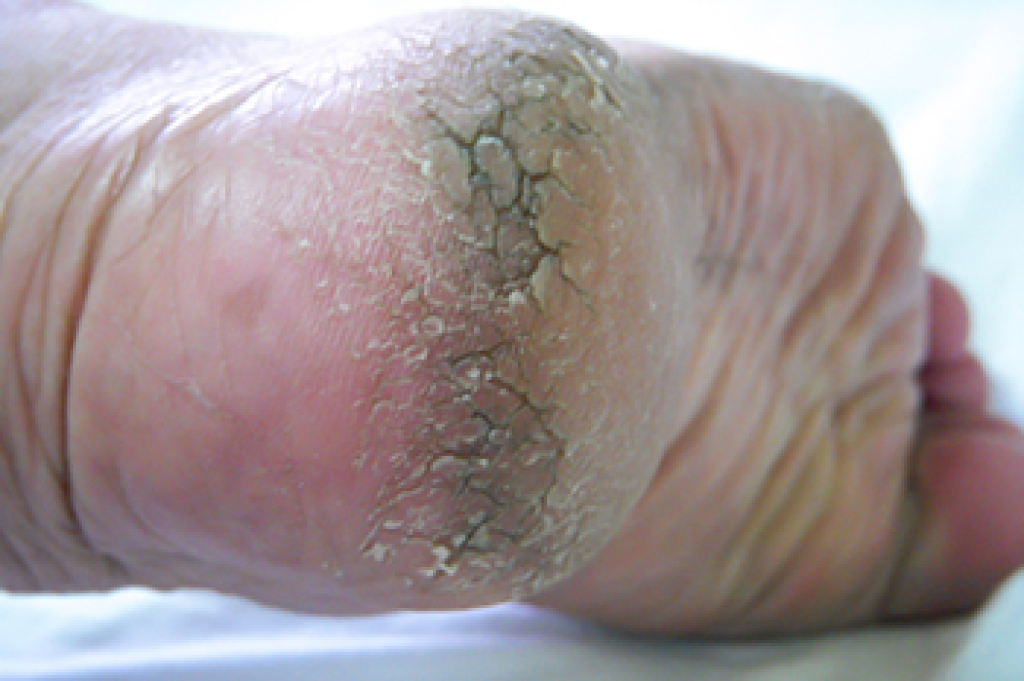

- Callus or corns on the bump

A bunion is a bony lump that forms on the side of the big toe. Bunions can be caused by several things like genetics or from wearing shoes that do not have adequate room for the toes to move freely in. This condition may also develop from a toe injury that caused the bones to misalign. Eventually, a callus may form over the bunion as a result of the bunion constantly rubbing against the inside of the shoes that are worn. Some patients find it beneficial to wear a protective covering over the bunion and many will also purchase larger shoes to accommodate it. Massaging the affected area may aid in keeping the toe flexible and the surrounding tissue soft. An effective massage can be rolling the foot on a tennis ball and performing foot exercises may help to strengthen the muscles in the toes too. It is easier to find shoes that fit properly if they are tried on at the end of the day when the feet are at their largest. If you see the first signs of a small bump developing on the side of the big toe, please consult with a podiatrist who can determine if it is a bunion and what the right treatment is for you.